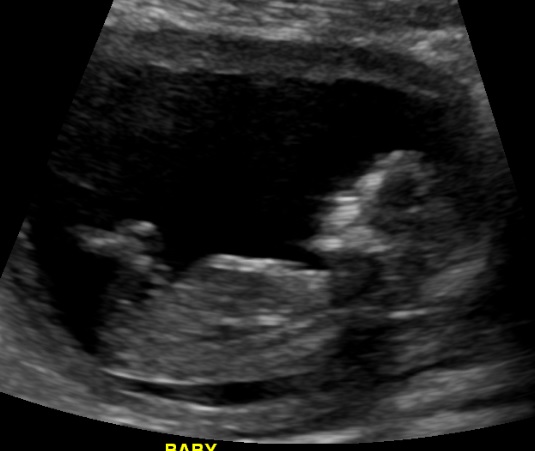

Hi ladies. We did IUI to conceive this baby. We had our NT scan on Tuesday and while I wanted to be team green to potentially avoid GD, the tech gave us a peek without asking if we wanted to. There didn't seem to be anything between the legs. My son's ultrasound was a well defined boy part at 15 weeks. I know this is earlier, but I don't want to get my hopes up. Or maybe baby had it tucked, or something. I was going through the pics they gave us and I'm confused by the nub. Can you help me? Thanks!

Attachment 25500

Exactly which gestation is this? I'm on the fence on this one.

Baby measuring 13+6 by CRL, by LMP 13+2.

I think I'm going for a slight boy lean on this one, my little boys nub shot was very similar to this.

I'm thinking since this is in week 13, I'll lean girl, even though I would lean more boy if it were around 12+0 weeks. GL!